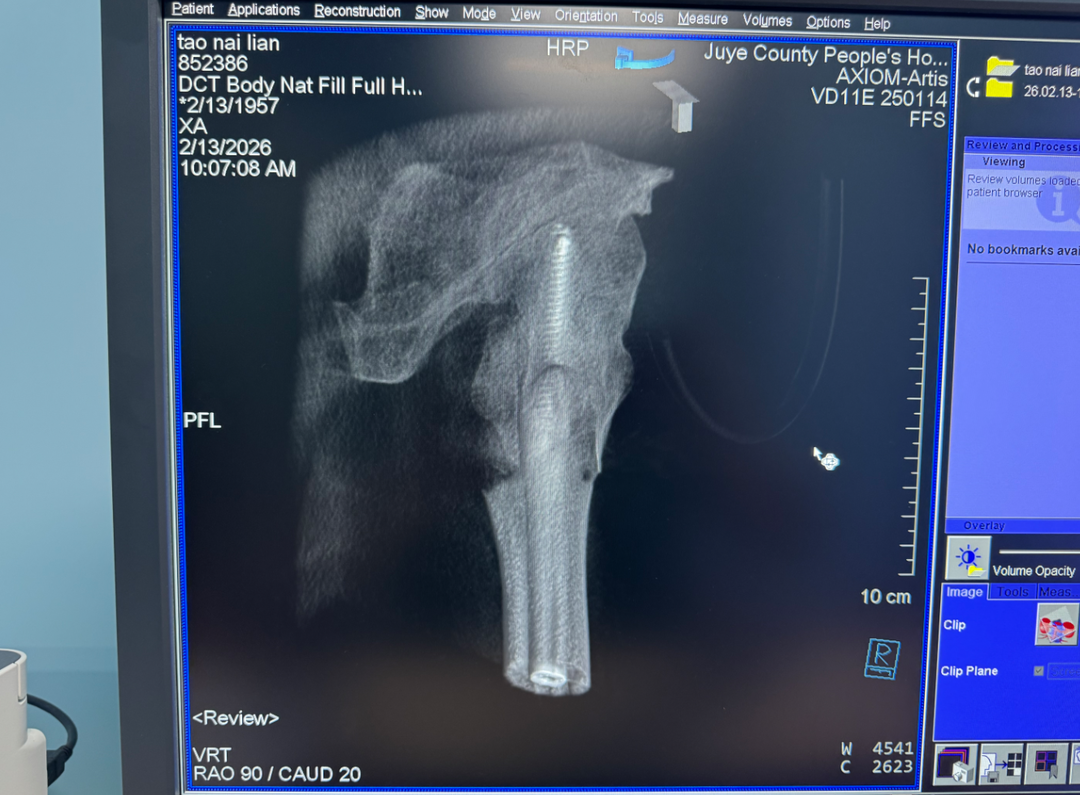

传统牵引床复位往往操作繁琐、耗时长、效果欠佳。而巨野县人民医院创伤骨科团队利用自研的骨折牵引复位器,可以在闭合状态下快速、精准地完成复位。术中,医生借助该复位器提供稳定的力学牵引,快速恢复骨折端的对位对线,再配合先进的微创髓内钉系统进行固定。

“手术时间较传统方式大幅缩短,切口小、出血少,固定却更加稳定。”主刀医生介绍道。由于采用了闭合复位技术,微创固定,这为术后“快速康复”奠定了坚实的基础。术后第二天,患者便可在床上进行下肢功能锻炼,并在医护人员指导下借助助行器尝试下地站立。